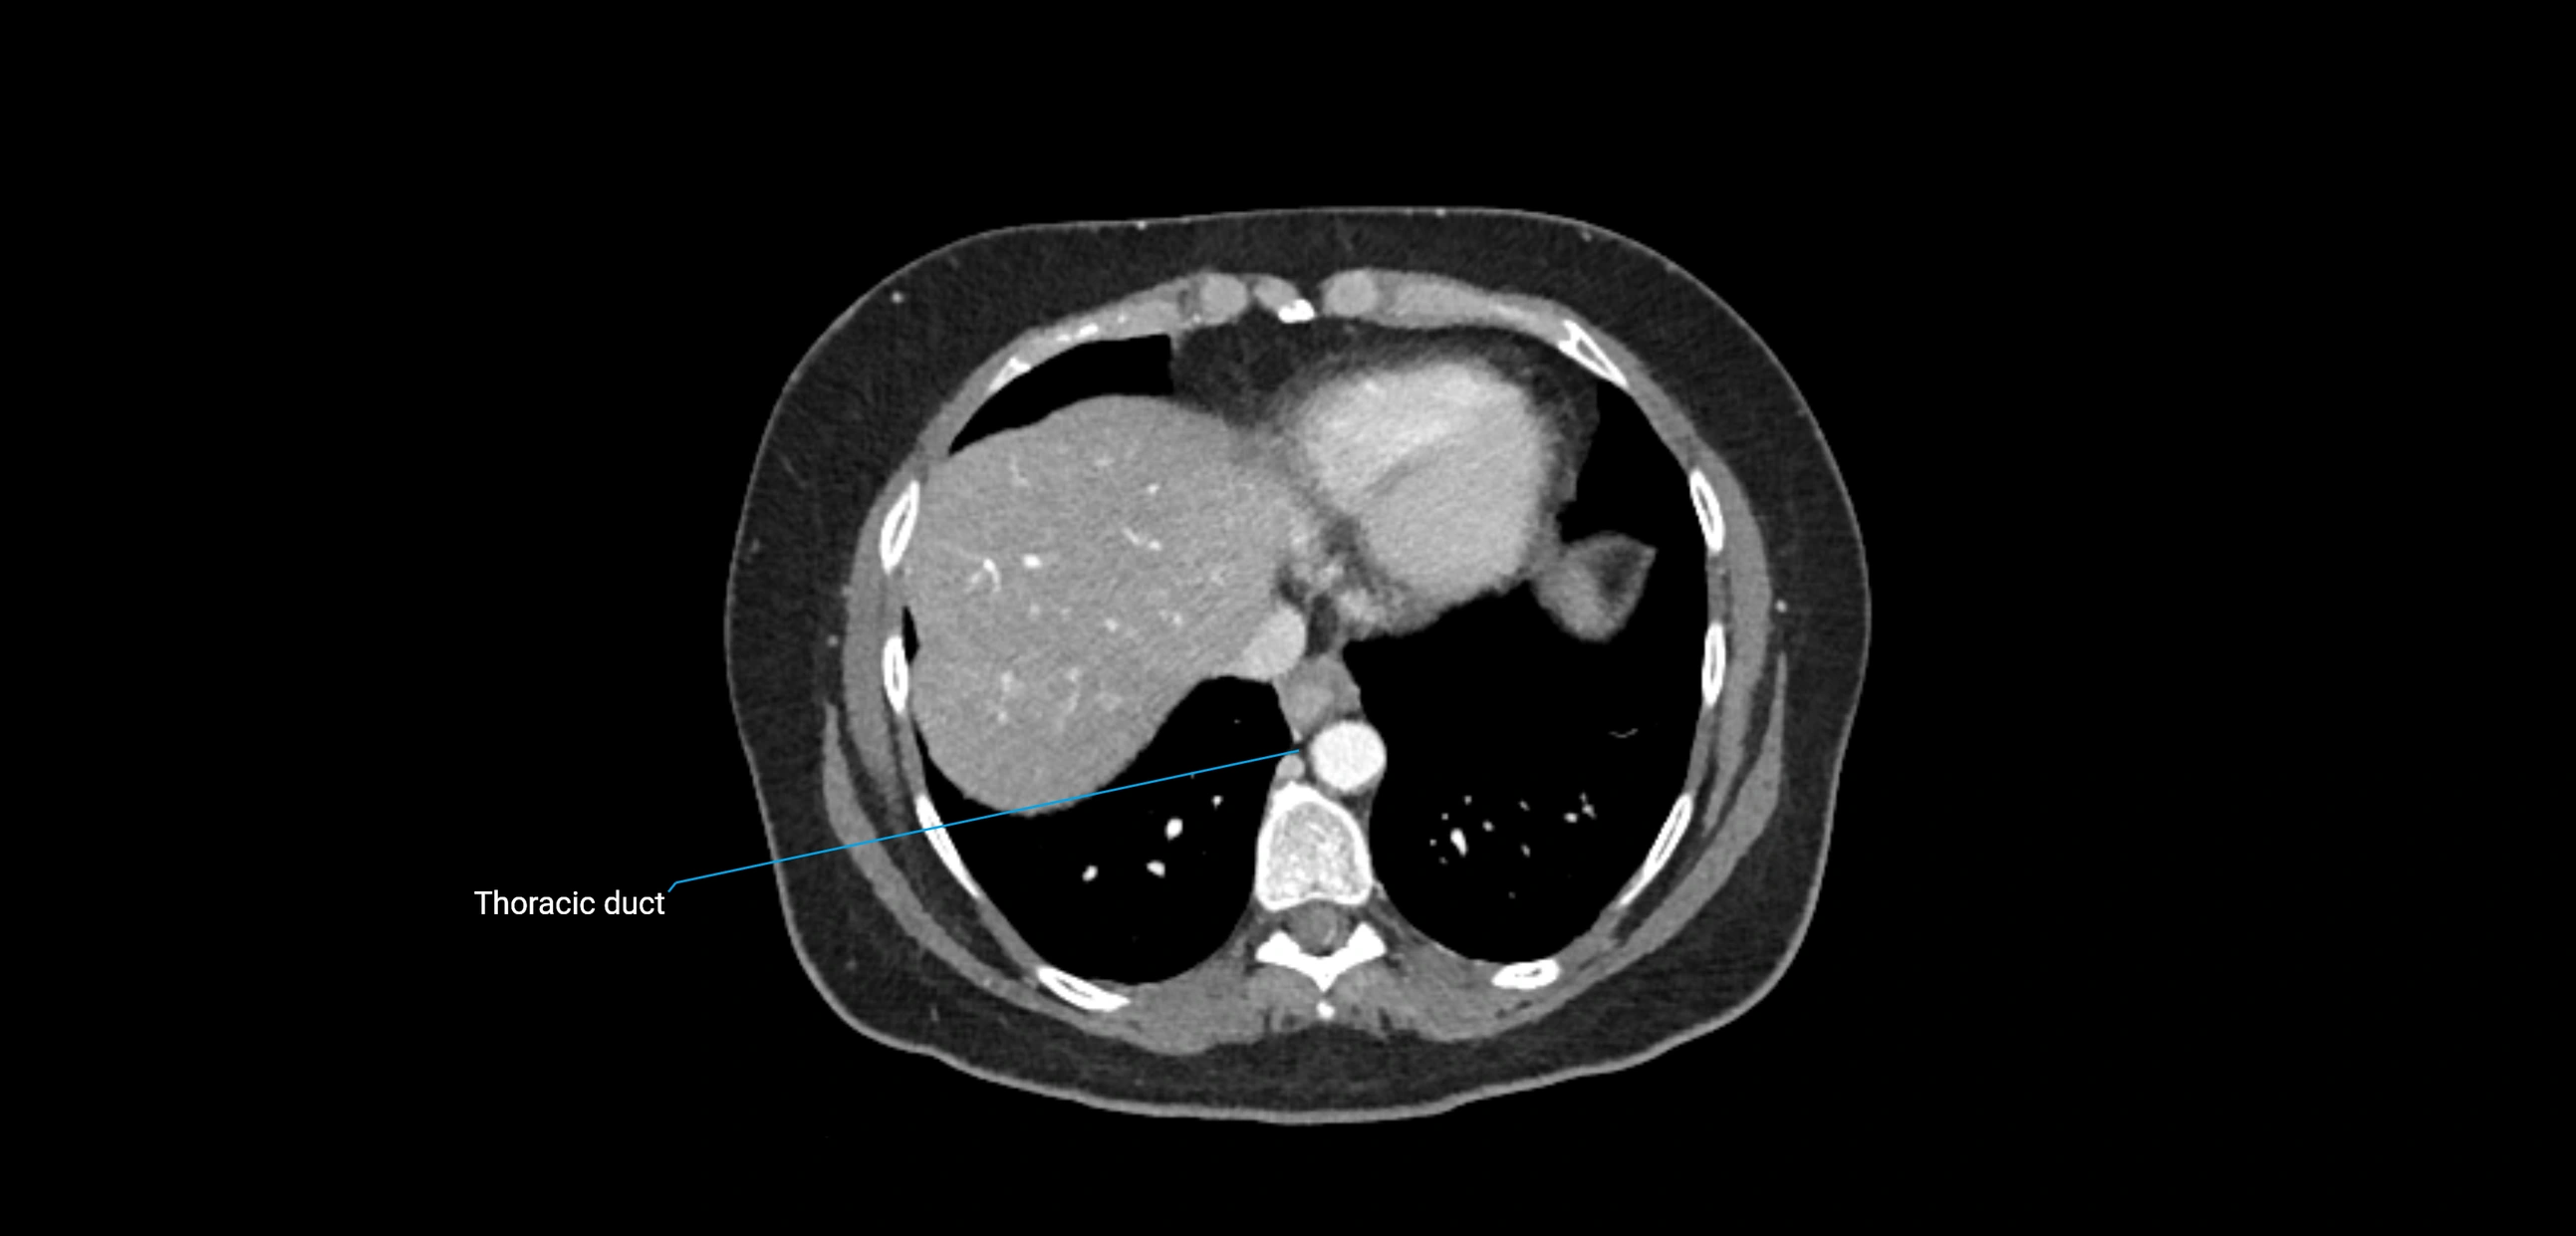

CT Appearance

CT Pre-Contrast:

• Nodes appear as soft-tissue density nodules adjacent to the aorta and IVC

• Calcification may be seen in chronic infections (e.g., tuberculosis)

CT Post-Contrast:

• Normal nodes enhance homogeneously

• Malignant nodes may show heterogeneous enhancement, central necrosis, or conglomerate formation

• Size >1 cm short axis is suspicious, though morphology and distribution are equally important

CT image

image